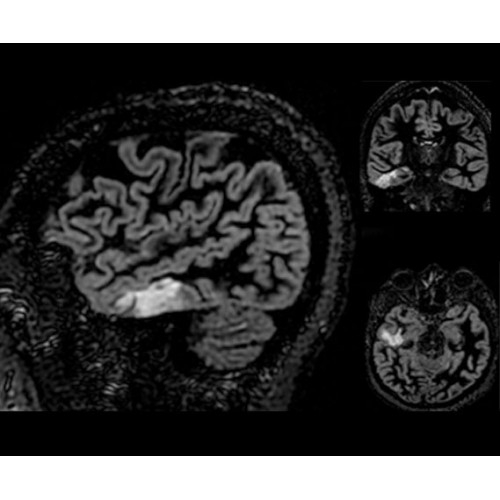

• NeuroWorks — универсальное решение для визуализации анатомии головного мозга, позвоночника, сосудов и периферических нервов с четкой дифференциацией тканей.

• 48-канальная катушка TDI для головы, входящая в базовую комплектацию SIGNA Architect, обеспечивает феноменальную производительность с учетом особенностей каждого пациента. Благодаря гибкому и универсальному дизайну, высокому соотношению сигнал/шум и передовым технологиям визуализации, таким как HyperWorks, учитываются потребности подавляющего большинства пациентов.